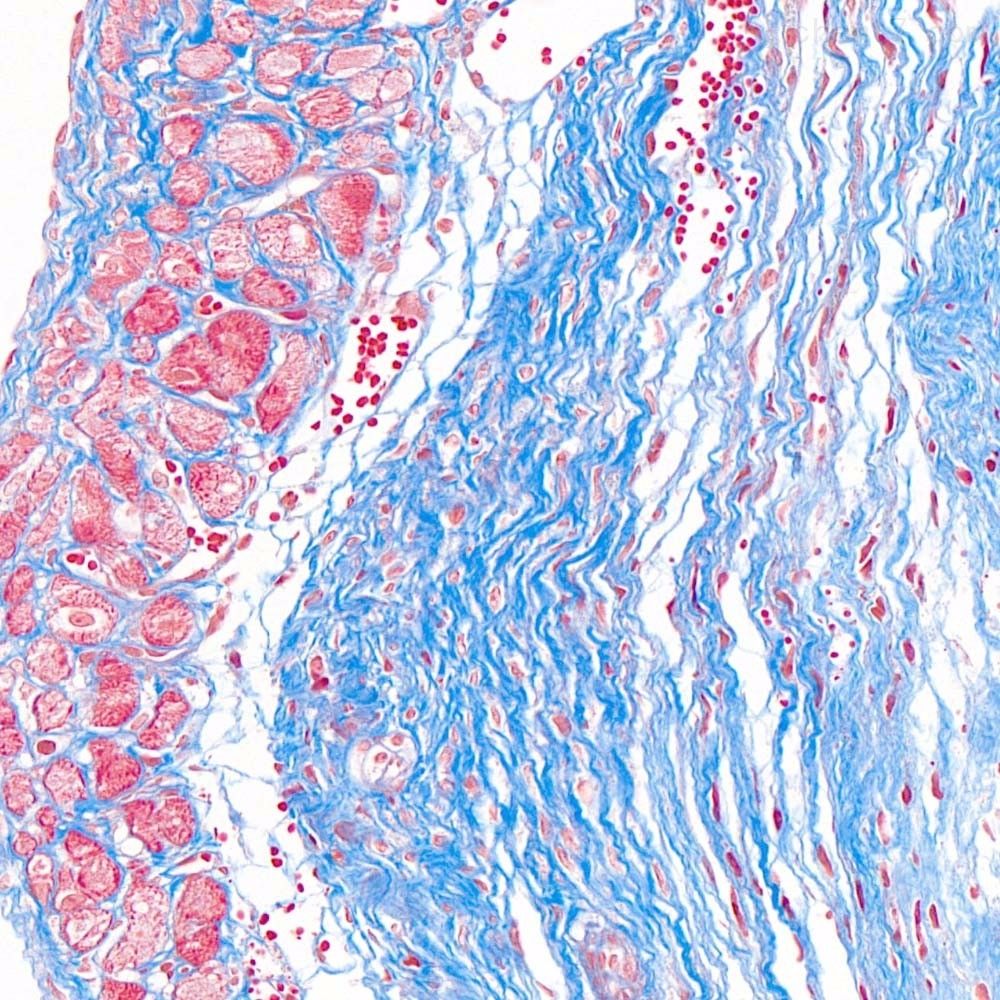

首先,讓我們深入探討MASSON染色的原理。MASSON染色的原理與陰離子染料分子的大小和組織的滲透性密切相關(guān)。染料的分子量決定了其穿透組織的能力:小分子量的染料更容易穿透結(jié)構(gòu)致密、滲透性較低的組織,而大分子量的染料則更傾向于進入結(jié)構(gòu)疏松、滲透性較高的組織。在MASSON染色中,由于肌纖維間隙較小,而膠原纖維間隙較大,因此小分子量的麗春紅染料更容易滲透進入肌纖維并使其呈現(xiàn)紅色,而大分子量的苯胺藍染料則主要進入膠原纖維并使其呈現(xiàn)藍色或綠色。

MASSON染色的陽性意義在于,它能夠幫助研究人員區(qū)分膠原纖維和肌纖維,從而觀察病變組織中纖維結(jié)締組織的增生和分布。當MASSON染色結(jié)果呈現(xiàn)陽性時,通常意味著局部組織中存在膠原纖維的增生。這種增生可能是由于局部皮膚出現(xiàn)炎癥或組織增生等病理 過程所導(dǎo)致的。因此,MASSON染色的陽性結(jié)果可以作為判斷組織纖維化程度的一個重要指標。